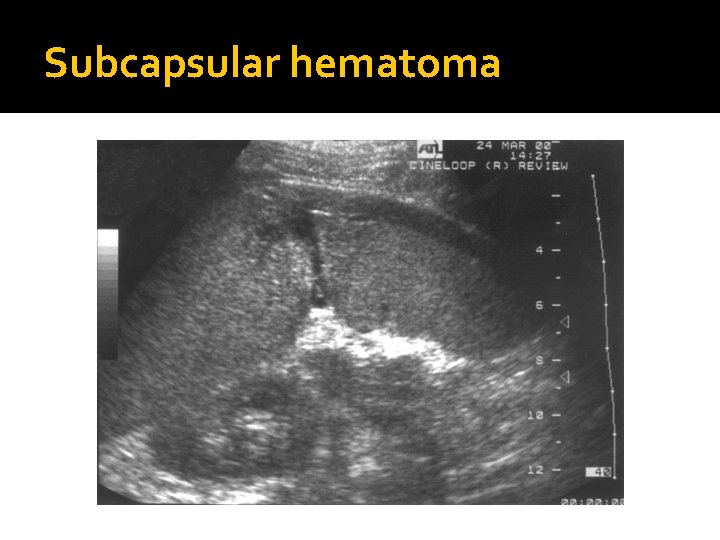

Trauma � Splenic trauma may result in a parenchymal or subcapsular hematoma or splenic laceration with associated hemoperitoneum. � Clinical symptoms depend on the extent of blood loss. � If the splenic capsule is intact, a subcapsular hematoma may be seen as a peripheral crescentshaped collection. � If the spleen is lacerated, a hemoperitoneum will occur which may be located in the LUQ or extend into the other peritoneal compartments, including the paracolic gutters, pelvis, and right side. Conservative management is preferred to spenectomy if the patient is clinically stable.

Splenic Trauma �Intraparenchymal or subcapsular hematomas result when the splenic capsule remains intact (DOES NOT RUPTURE).

Subcapsular hematoma

What type of hematoma is the result of splenic trauma in which the splenic capsule remains intact? �An intra-parenchymical or sub-capsular hematoma occurs with splenic trauma in which the splenic capsule remains intact.